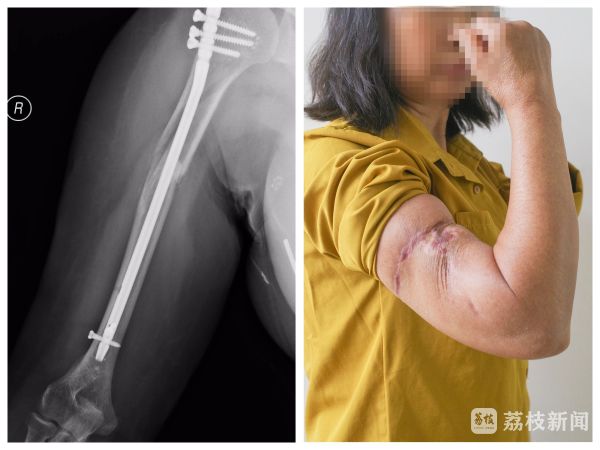

三个月前的大雨天,张女士骑车回家时不慎滑倒,右上臂瞬间传来剧烈疼痛。老家医院的X光片显示:肱骨骨折。本以为微创手术固定后就能顺利康复,可术后她却发现,手腕和手指完全不听使唤,怎么也抬不起来。老家医生也慌了神,因为这样的症状意味着桡神经出现了问题,这是肱骨骨折以后最严重的一个并发症。

带着焦虑,张女士转诊至南京市第一医院骨科(含手外科)。住院后,骨科医生们围绕她的病情展开了激烈讨论。由于她接受的是微创髓内钉固定术,术中并未显露桡神经,如今出现神经损伤症状,医生们的意见也分成了两派:一种观点认为,微创骨折内固定对神经的干扰很小,理论上神经有自我恢复的可能,应该保守观察至少3个月,避免贸然手术增加创伤;另一种观点则认为必须立刻手术探查,若神经已断裂或严重挫损,拖延只会错失治疗良机。

接到会诊请求后,超声医学科肌骨超声团队立即为张大姐做了详细检查。探头在她的胳膊上仔细滑动、多方向扫描,最终团队医生笃定地告诉她:“桡神经连续性完好,没有断裂!只是受骨折刺激出现了水肿增粗,恢复机会很大。”听到这个消息,张女士悬着的心终于放下一半。杨蓊勃也明确表示:“暂时不用二次手术,给神经一点自我修复的时间。”

三个月后,张女士再次走进骨科诊室时,脸上满是笑容。在超声医学科和骨科的共同帮助下,她成功避免了二次手术,手腕功能已基本恢复,正处于康复阶段,对康复至术前状态充满了信心。——肌骨神经健康“看得见”的守护者